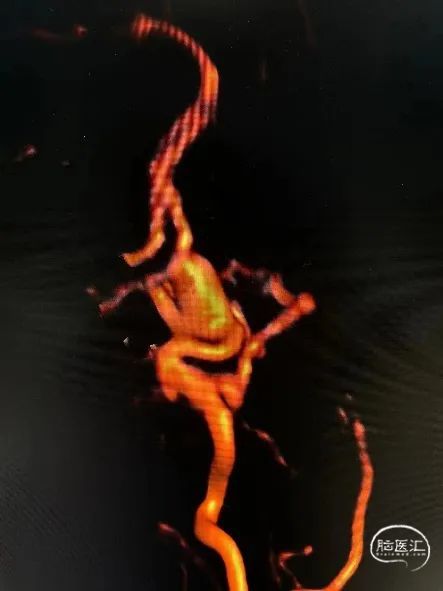

术前MRA提示左侧眼动脉段动脉瘤。

动脉瘤相对窄颈,拟先行弹簧填塞后行Surpass Evolve血流导向装置植入。

造影评估证实左侧眼动脉段动脉瘤,标记测量动脉瘤最大径13mm,动脉瘤颈5.6mm;近端血管直径4.3mm,远端3.8mm,后交通至海绵窦段后部长度24mm。压颈显示前交通开放。